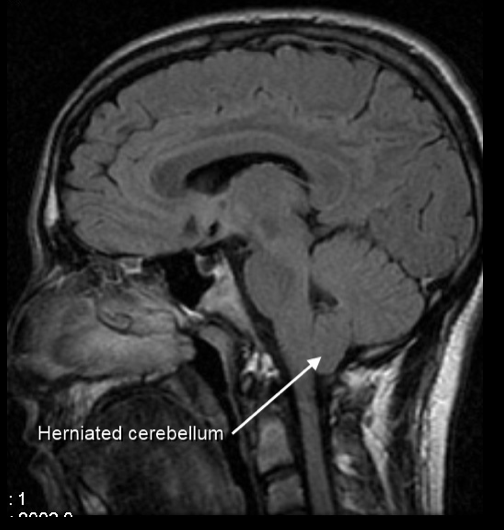

Como caracteriza-se o nistagmo downbeat e qual a localização típica da lesão?

Nistagmo vertical com fase rápida para baixo

Pensar em lesão na junção cervicomedular, como a mal-formação de Arnold-Chiari